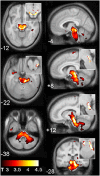

To explore brain involvement in chronic fatigue syndrome (CFS), the statistical parametric mapping of brain MR images has been extended to voxel-based regressions against clinical scores. Using SPM5 we performed voxel-based morphometry (VBM) and analysed T(1) - and T(2) -weighted spin-echo MR signal levels in 25 CFS subjects and 25 normal controls (NC). Clinical scores included CFS fatigue duration, a score based on the 10 most common CFS symptoms, the Bell score, the hospital anxiety and depression scale (HADS) anxiety and depression, and hemodynamic parameters from 24-h blood pressure monitoring. We also performed group × hemodynamic score interaction regressions to detect locations where MR regressions were opposite for CFS and NC, thereby indicating abnormality in the CFS group. In the midbrain, white matter volume was observed to decrease with increasing fatigue duration. For T(1) -weighted MR and white matter volume, group × hemodynamic score interactions were detected in the brainstem [strongest in midbrain grey matter (GM)], deep prefrontal white matter (WM), the caudal basal pons and hypothalamus. A strong correlation in CFS between brainstem GM volume and pulse pressure suggested impaired cerebrovascular autoregulation. It can be argued that at least some of these changes could arise from astrocyte dysfunction. These results are consistent with an insult to the midbrain at fatigue onset that affects multiple feedback control loops to suppress cerebral motor and cognitive activity and disrupt local CNS homeostasis, including resetting of some elements of the autonomic nervous system (ANS).